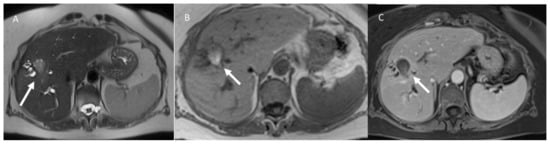

- Granata, V.; Grassi, R.; Fusco, R.; Setola, S.; Belli, A.; Piccirillo, M.; Pradella, S.; Giordano, M.; Cappabianca, S.; Brunese, L.; et al. Abbreviated MRI Protocol for the Assessment of Ablated Area in HCC Patients. Int. J. Environ. Res. Public Health 2021, 18, 3598. [Google Scholar] [CrossRef]